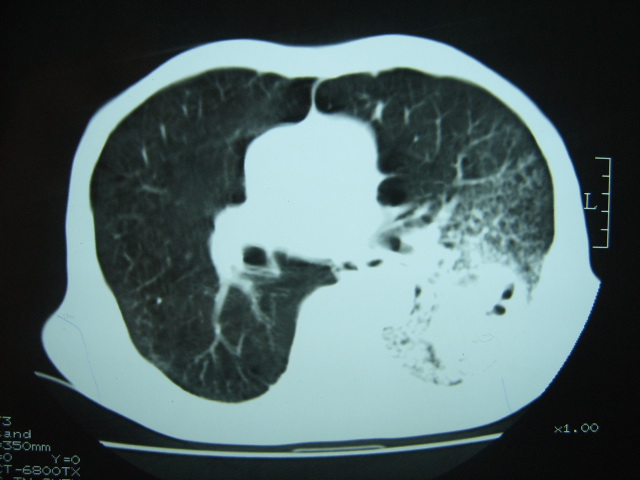

男74岁,咳嗽,寒战,低烧。有糖尿病史。

两肺结核,空洞形成,左下肺肺段隔离症待排

1、左下肺肺脓肿,合并霉菌球形成?.2、双肺陈旧性病灶.3、右上肺病灶警惕瘢痕癌,建议定期复查.

两肺结核,左下肺空洞性病变,结核性?炎性?癌性?抗炎治疗后复查。

两肺结核,左下肺大片实变,内见空洞性病变,壁不规则,结合糖尿病史,考虑:结核性?霉菌性?建议结合实验室检查或治疗后复查。